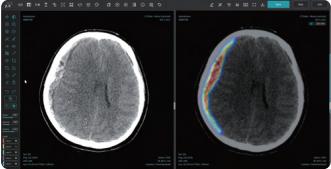

비조영 CT 영상 분석 뇌 경막하 출혈 탐지 솔루션 JLK-SDH

의료 인공지능(AI) 기업 제이엘케이는 올해 본격적인 미국 진출 계획의 일환으로 현지에서 수요가 많은 CT영상 기반 뇌 경막하 출혈 분석 솔루션 JLK-SDH를 새롭게 출시했다고 29일 밝혔다.

JLK-SDH는 뇌를 둘러싼 경막 내부 혈관의 파열로 인한 출혈을 진단할 수 있는 솔루션으로 주로 낙상이나 교통사고 등 외상으로 발생하는 경막하 출혈 환자의 신속하고 정확한 병변 분석을 위해 개발됐다. 일반적으로 경막하 출혈 환자는 두부 외상으로 응급실로 이송되는 경우가 빈번하기에 가장 먼저 CT 촬영을 진행해 진단을 하고 치료 계획을 수립하게 된다.

기존 뇌출혈 진단 솔루션인 JLK-ICH가 주로 전반적인 급성 뇌출혈 진단에 강점을 보인 반면 이번에 출시된 JLK-SDH는 CT에서 신호강도가 강하지 않아 정상 뇌와 구분이 어려운 아급성(subacute) 혹은 만성 경막하출혈 데이터 학습에 공을 들여 어려운 뇌출혈 진단에 강점이 있다고 회사 측은 설명했다.

JLK-SDH는 미국 의료기관의 뇌졸중 진단 시 CT 촬영이 많은 것에 착안해 보강된 CT 솔루션으로, 회사는 미국 시장 진출에 더욱 박차를 가할 계획이다. 미국의 CT 촬상 건수는 연간 8600만 건으로 경쟁사인 비즈 AI(Viz AI)의 CT 기반 인공지능 뇌졸중 솔루션의 한 건당 보험수가는 1040달러(약 140만 원)로 책정돼 있다.

제이엘케이는 CT, MRI 등 다양한 솔루션으로 뇌졸중 전주기를 커버할 수 있는 강점을 적극적으로 내세운다는 전략이다.

김동민 제이엘케이 대표는 "응급 상황에서 빠르고 정확한 진단과 치료를 할 수 있도록 돕는 JLK-SDH 출시로 미국시장 진출에 유용하게 활용될 CT 기반의 뇌출혈 솔루션을 모두 갖췄다. JLK-SDH의 빠른 미국 식품의약국(FDA) 인허가 신청을 위해 집중하고 현지 상황에 맞는 진출 전략을 구상해 미국 시장 선점을 위한 최선의 노력을 다하겠다"고 말했다.